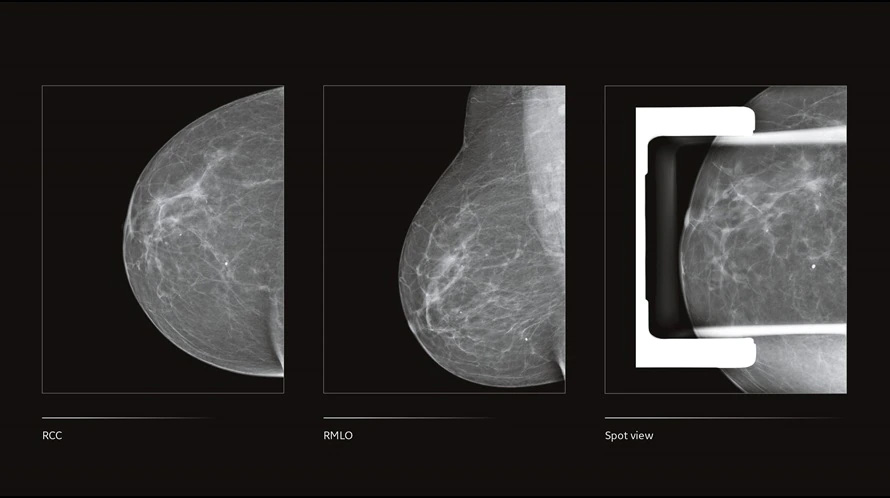

GE Senographe Crystal Nova — полноформатная цифровая маммографическая система, созданная для центров раннего выявления и специализированных отделений лучевой диагностики. Используется высокоэффективный детектор с повышенной детективной квантовой эффективностью, архитектура системы позаимствована у премиальных линеек GE, что обеспечивает стабильное качество визуализации при низкой дозовой нагрузке. Автоматическая оптимизация параметров экспозиции (AOP) подстраивает напряжение и ток рентгеновской трубки под плотность и толщину груди, а программная обработка eContrast улучшает локальный контраст без усложнения рабочего процесса.

Система ориентирована на высокую пропускную способность кабинета: эргономичная стойка с моторизованным перемещением С-дуги, компактный пост управления и продуманная организация поля обзора упрощают укладку пациентов и смену проекций. Интегрированная рабочая станция с преднастроенными протоколами, встроенными инструментами контроля качества и расширенной DICOM-совместимостью облегчает включение комплекса в существующую ИТ-инфраструктуру. Маммографическая система поддерживает широкий набор компрессионных пластин и опций для увеличения, прицельных и локализационных снимков, а также конфигурации с 2D-биопсией, что делает Senographe Crystal Nova универсальным решением для скрининга и уточняющей диагностики.

- Алгоритм обработки eContrast для усиления локального контраста и повышения читаемости деталей паренхимы.

- Набор стандартных и малых компрессионных пластин, опции для увеличения, прицельных и специализированных исследований, включая конфигурации для 2D-биопсии.